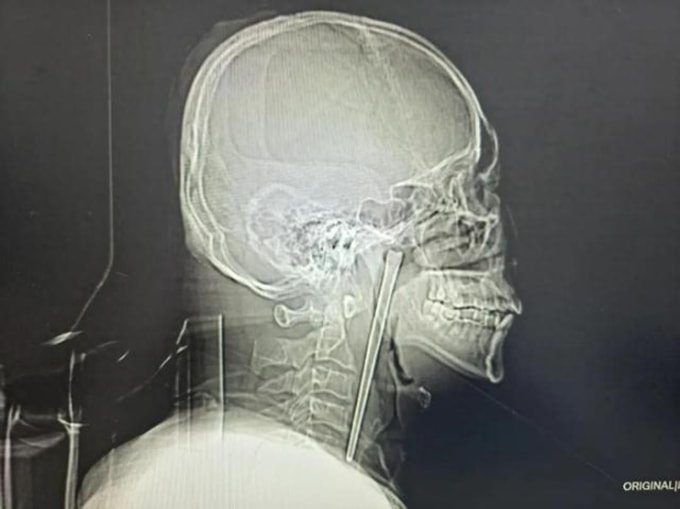

Kết quả khám cho thấy chiếc đũa kim loại nằm sâu trong vòm miệng mềm của bệnh nhân. Song lớp niêm mạc xung quanh may mắn không bị tổn thương nghiêm trọng và các cơ quan lân cận không bị di lệch. Các bác sĩ xác nhận dây thanh quản của bệnh nhân vẫn hoạt động bình thường. Do ông Vương không đồng ý phẫu thuật hở ở vùng cổ, các bác sĩ đã lên phương án can thiệp tối thiểu để lấy dị vật qua đường miệng. Ca phẫu thuật diễn ra thuận lợi với lượng máu mất không đáng kể. Chiếc đũa kim loại dài 12 cm cuối cùng đã được đưa ra ngoài thành công. Ông Vương hồi phục tốt và được xuất viện vài ngày sau đó.